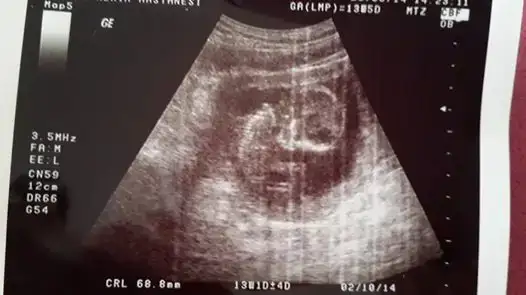

selam kızlar daha once burada usg goruntulerını paylasmıstım :) net sonucu yazayım dedım,erkek..

Eki Görüntüle 1016535

Eki Görüntüle 1016536 Eki Görüntüle 1016536